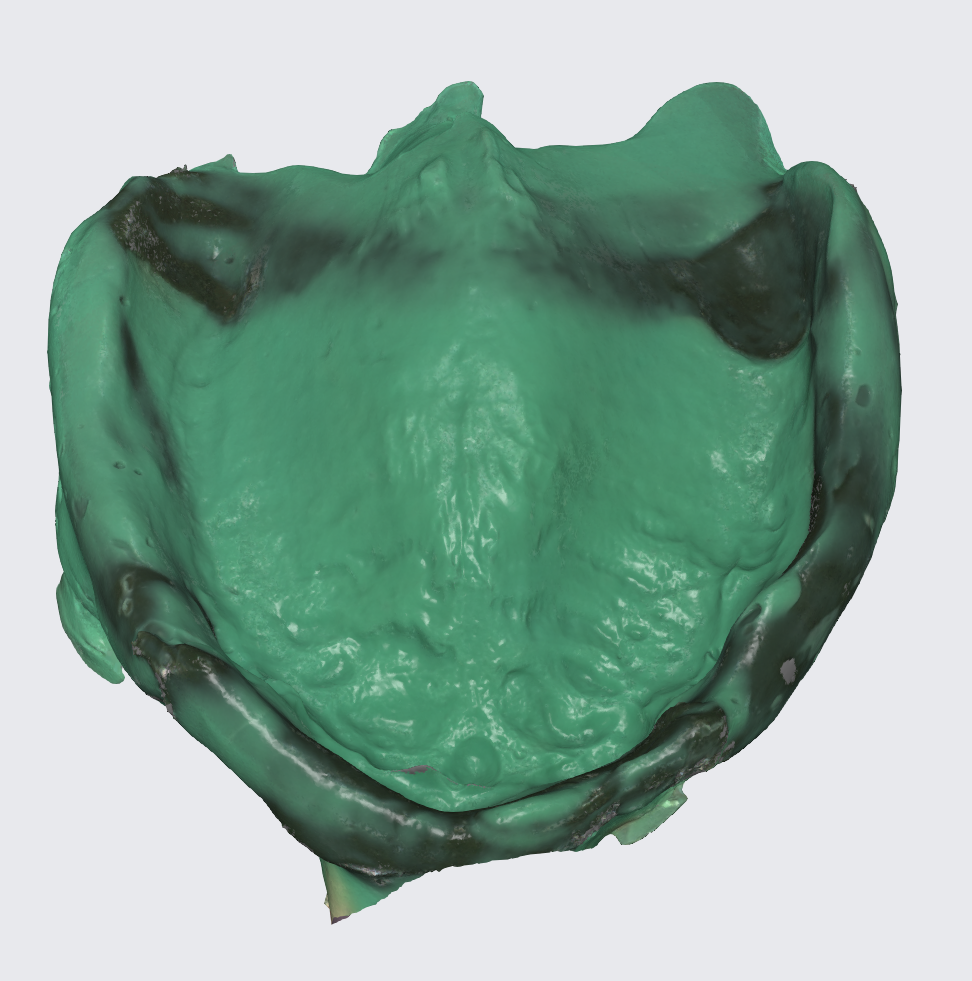

This tray was used for border molding and analog impression and then scanned with a lab scanner as seen in the next photo.

To prepare for the maxillary all on X procedure patient had the upper denture relined with impression material and also multiple dots of radio opaque filling material where temporarily placed on the said denture. Then the 2 dentures where scanned. Also scans of the healed tissues and of the face where recorded.

Using the Aoralscan Elite intraoral scanner (Shining 3D), detailed scans of edentulous ridges and interim prostheses were recorded efficiently and accurately. Edentulous arch scanning proved precise and rapid, significantly simplifying the workflow.

Another view of the post graft healing in the mandibular arch and visibility of the composite marker additions done on the upper denture for alignment purposes between scan image and CBCT datasets.